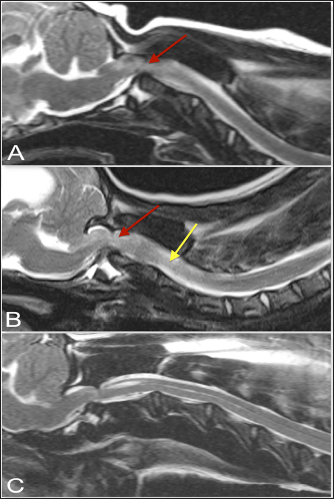

Further characterization of the dens was performed and the presence of abnormal intramedullary hyperintensity, hydrocephalus, Chiari-like malformation, and syringohydromyelia were documented (Figs. 3 and 4). The presence or absence of dens was noted, including whether the dens appeared hypoplastic. Hydrocephalus was characterized by assessment of lateral cerebral ventricular distension, when the field of view included the brain and was subjectively graded as mild, moderate, or severe. Syringohydromyelia was considered present if the central canal diameter or fluid-filled cavities in the spinal cord exceeded 2 mm, and evaluated as focal or extensive, with distinct or indistinct margins (Cappello and Rusbridge, 2007). Chiari-like malformation was classed as absent, indentation of the caudal aspect of the cerebellum, or herniated (impaction of cerebellar vermis through the foramen magnum), based on a previously reported grading scheme (Rusbridge et al., 2000).

Fig. 4. T-2 weighted sagittal images of three dogs affected by an atlanto-axial subluxation in this study (TE, 120 ms; TR, 3800 ms; slice thickness, 2.5 mm). (A) This dog with atlantoaxial subluxation has intramedullary T2 hyperintensity at the level of compression that likely indicates edema or ischemia (red arrow). Chiari malformation is absent. (B) There is Chiari malformation causing impaction of the cerebellum, with similar intramedullary hyperintensity at the level of compression as in A (red arrow) but additional pre-syrinx formation caudal to the level of spinal cord compression (yellow arrow). This dog was also graded as having moderate hydrocephalus. (C) There is Chiari malformation causing indentation of the cerebellum and focal syringomyelia greater than 2 mm in diameter.